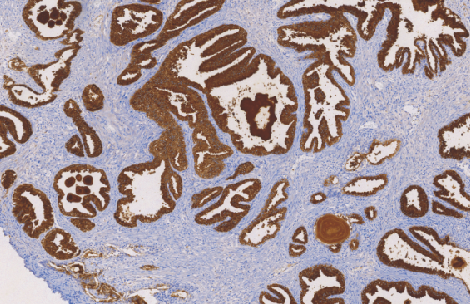

Prostate Specific Antigen(PSA)鼠抗人前列腺特异性抗原单克隆抗体

前列腺特异性抗原(PSA)是一种分子量为34KD的蛋白属于丝氨酸蛋白酶的激肤释放酶家族,最初从人的精液中分离和纯化。后来发现它与从前列腺中分离出的蛋白免疫学方面相同并且生物学方面相似。PSA与前列腺酸性磷酸酶不同。据报道,PSA在非前列腺组织和肿瘤如乳腺癌中低水平表达

- 阳性部位:胞质

- 适用组织:石蜡切片

- 预处理:热修复